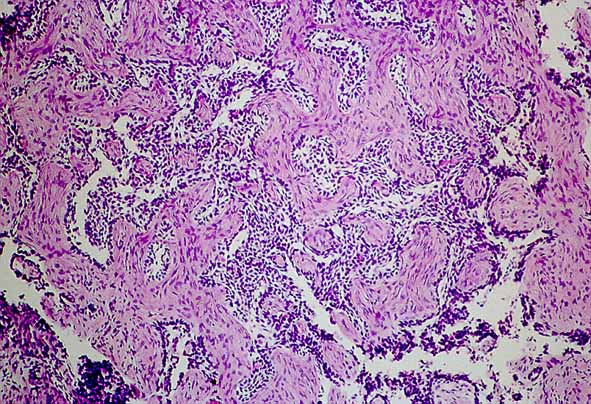

Figura 1